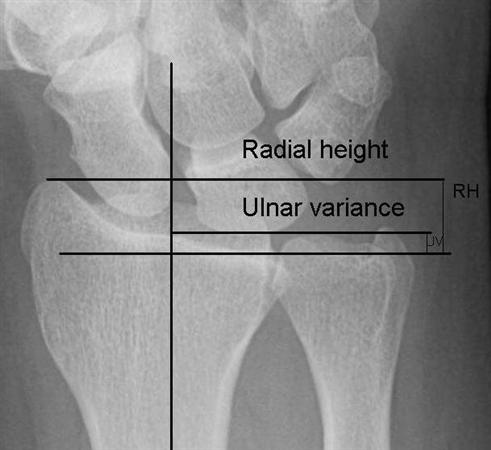

육체노동을 많이하는 남자에서 생기는 질환입니다. ulnar impaction syndrome 과는 반대로 ulna variance가 음성인 경우가 많으며

Lunate 의 sclerosis가 발견되면 Stage II 이며 Joint leveling 이 핵심입니다. ulna 변위가 중립 혹은 양성인 경우에는 radial wedge osteotomy나 그 외의 치료를 시행해 볼 수 있습니다.